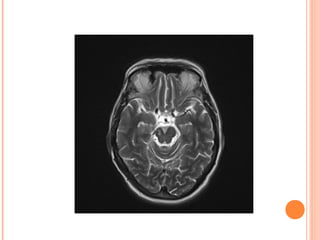

[123I]FP-CIT SPECT (DAT

SCAN)

Normal Abnormal

caudate

putamen

[123I]FP-CIT SPECT (DAT SCAN) NormalAbnormal caudate putamen